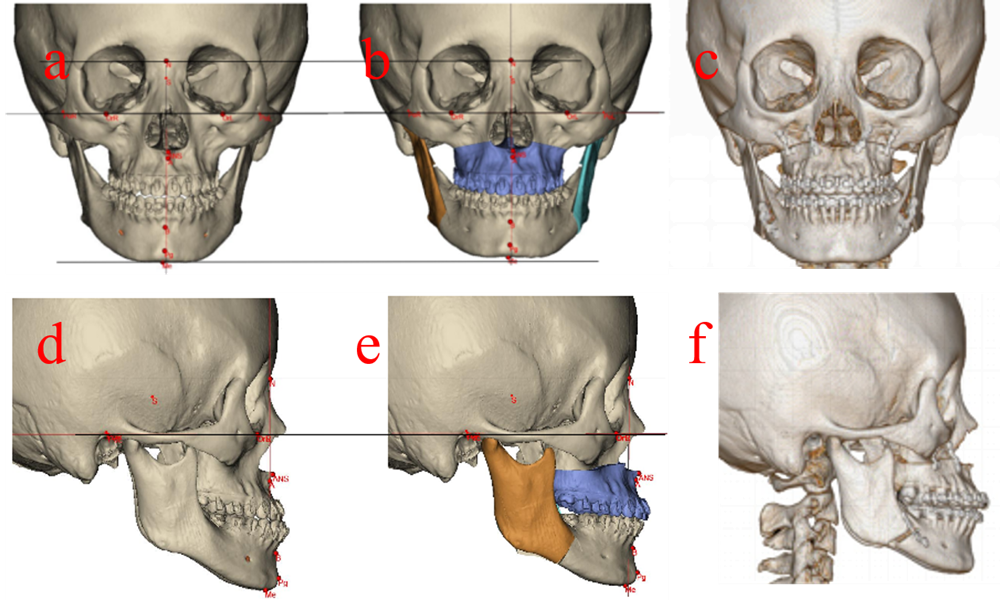

Figure 1. Surgical correction of maxillary retrusion with mandibular protrusion. a: preoperative frontal CT image. b: preoperative digital design and simulation. c: postoperative frontal CT image. d: preoperative lateral CT image. e: preoperative digital design and simulation. f: postoperative lateral CT image.